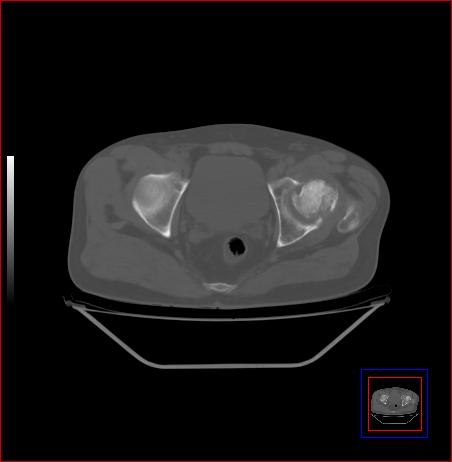

标题: CT15143:髋关节结核?

男,49,髋关节疼痛1年,无肺结核。

骨质破坏,硬化,周围软组织脓肿,关节间隙增宽,支持骨结核

支持:左侧髋关节结核合并轻度半脱位!

支持 左侧髋关节结核并半脱位。